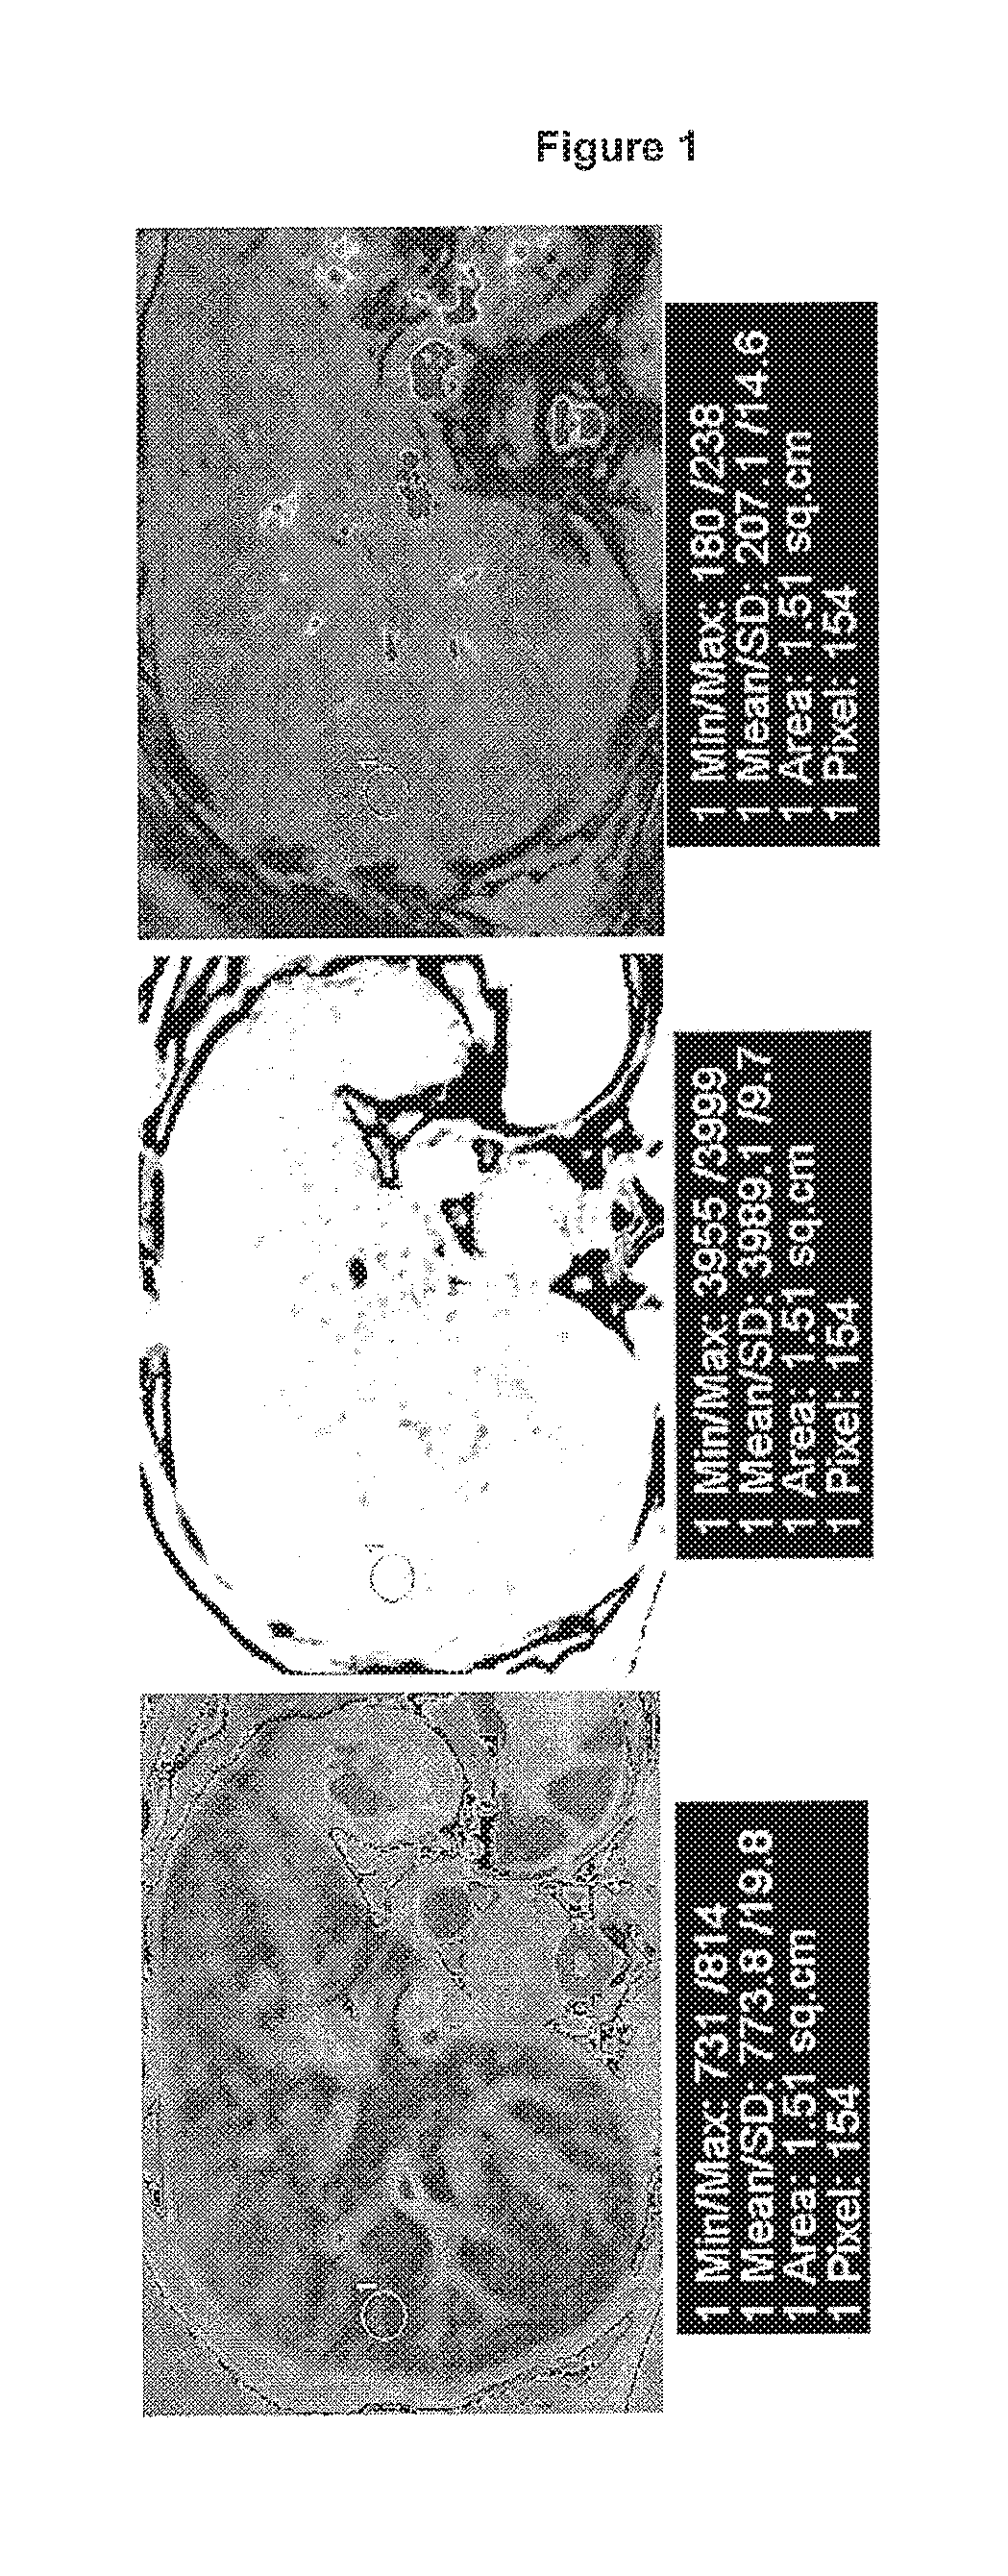

Medical imaging